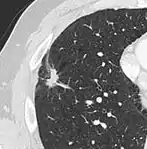

Lobulated nodule.[9]